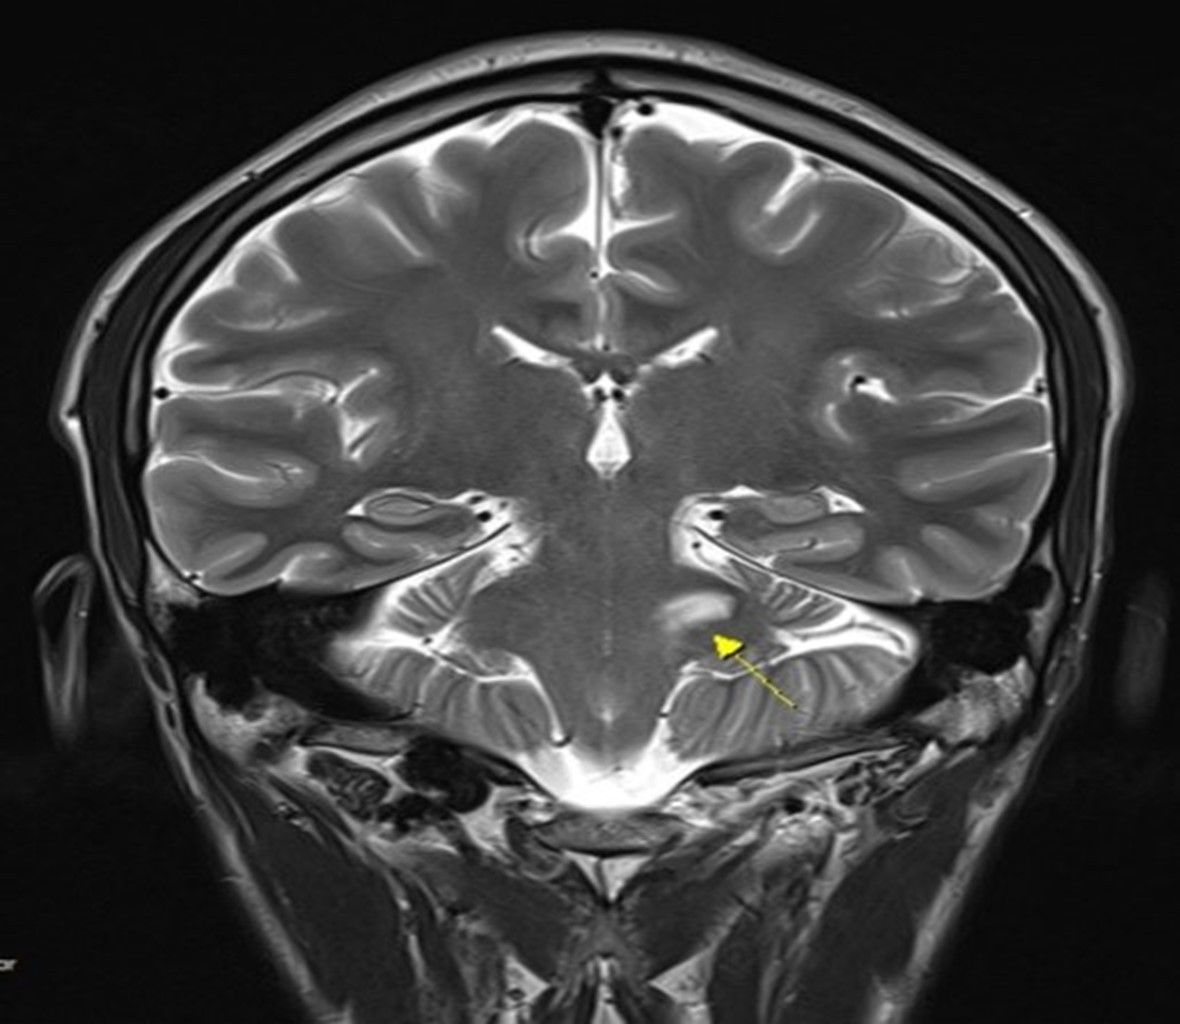

그림12.jpg 촬영 일시: 2025.05.11

<Fig 3. 뇌MRI (좌측 삼차신경핵 부위 고강도 영상 신호)>

왼쪽 소뇌의 삼차신경 부위에서 이상 신호가 확인되었습니다.

이건 중추신경계 문제나

종양 가능성을 시사하는 소견이었어요.

이번 환자분의 경우,

일반 MRI에서는 초기에 발견되지 않았던 병변이

조영제 강화 MRI에서 명확하게 확인되었어요.

혈관 검사인 MRA도 마찬가지로 중요한 정보를 제공하지만,

조직 자체의 문제는 MRI가 더 잘 보여줍니다.